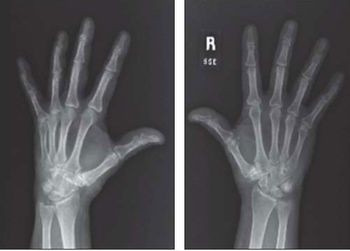

Radiographically occult wrist fractures, polypharmacy, invasive infection and hepatocellular carcinoma in HIV-infected patients. . . . here: a variety of subjects for you to test your clinical range.

Alpine skiing, snowboarding, bobsledding, ice hockey … the ongoing Winter Olympics in Sochi serve as a cold reminder that injuries plague athletes around the world. Test your knowledge of common sports injuries here.

Bone problems run the gamut from low bone density and osteoporosis to sports and exercise injuries to congenital disorders. Take this week’s photo quiz to test your knowledge of bone disease and related concerns.